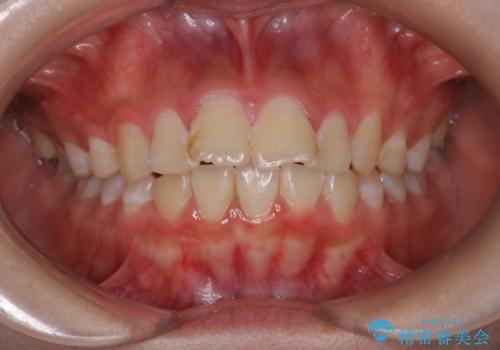

- 前歯が出ていることを主訴に来院されました。

インビザラインにて奥歯の遠心移動を行いながら最大限前歯が下がるように治療を行いました。

今回は遠心移動とIPRによってここまで前歯を下げることができました。